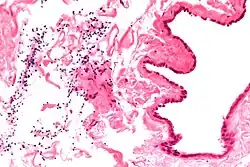

Spermatocele

Spermatocele is a fluid-filled cyst that develops in the epididymis.[3] The fluid is usually a clear or milky white color and may contain sperm.[4] Spermatoceles are typically filled with spermatozoa[5] and they can vary in size from several millimeters to many centimeters. Small spermatoceles are relatively common, occurring in an estimated 30 percent of males.[6] They are generally not painful. However, some people may experience discomfort such as a dull pain in the scrotum from larger spermatoceles.[7] They are not cancerous, nor do they cause an increased risk of testicular cancer. Additionally, unlike varicoceles, they do not reduce fertility.[7]